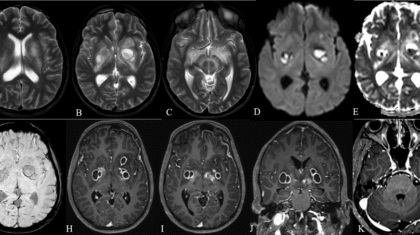

A 21 year old male was brought for evaluation of fever since 45 days associated with holocranial headache for 30 days and altered sensorium for 20 days .Working clinical diagnosis of chronic meningoencephalitis was made for which cross sectional imaging was requested.